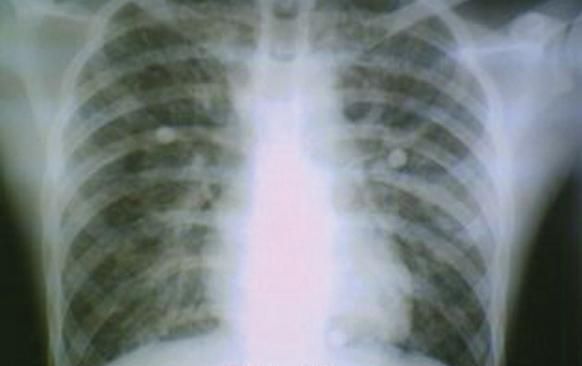

Chest radiographs, obtained daily, showed diffuse bilateral alveolointerstitial infiltrates (Figure 1); a moderate bilateral pleural effusion occurred during the second week of hospitalization (Figure 2).

Figure 1 - This radiograph illustrates diffuse bilateral alveolo-interstitial infiltrates.